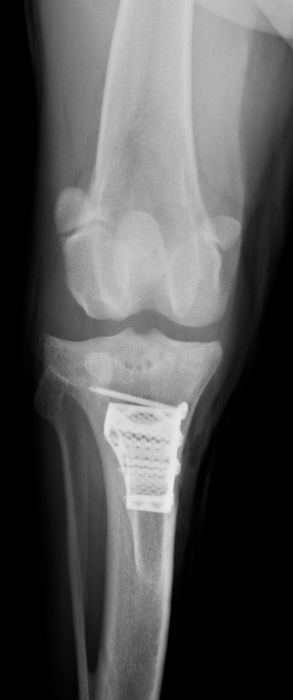

骨折治療について

動物も人間と同じように骨折や脱臼をします。

原因として交通事故などの大きな外力によるものもありますが、日本では小型犬が主体となっているため、ソファや抱っこしている所からの落下といった比較的小さな外力でも生じることが多くなっています。

骨折や脱臼の治療は、ギプスなどの処置のみで済むケースもありますが、ほとんどのケースは完全骨折や脱臼を生じますので、手術が必要となります。

当院における骨折治療は、動物のステータス、骨折の発生部位や分類などを考慮して「髄内ピン」「骨プレート」「創外固定器」を単独もしくは組み合わせて使用することで適当な固定力を得られるように施術しています。

●骨プレート

ステンレス製もしくはチタン製の金属の板(プレート)と骨ネジ(スクリュー)を使用して固定を行います。